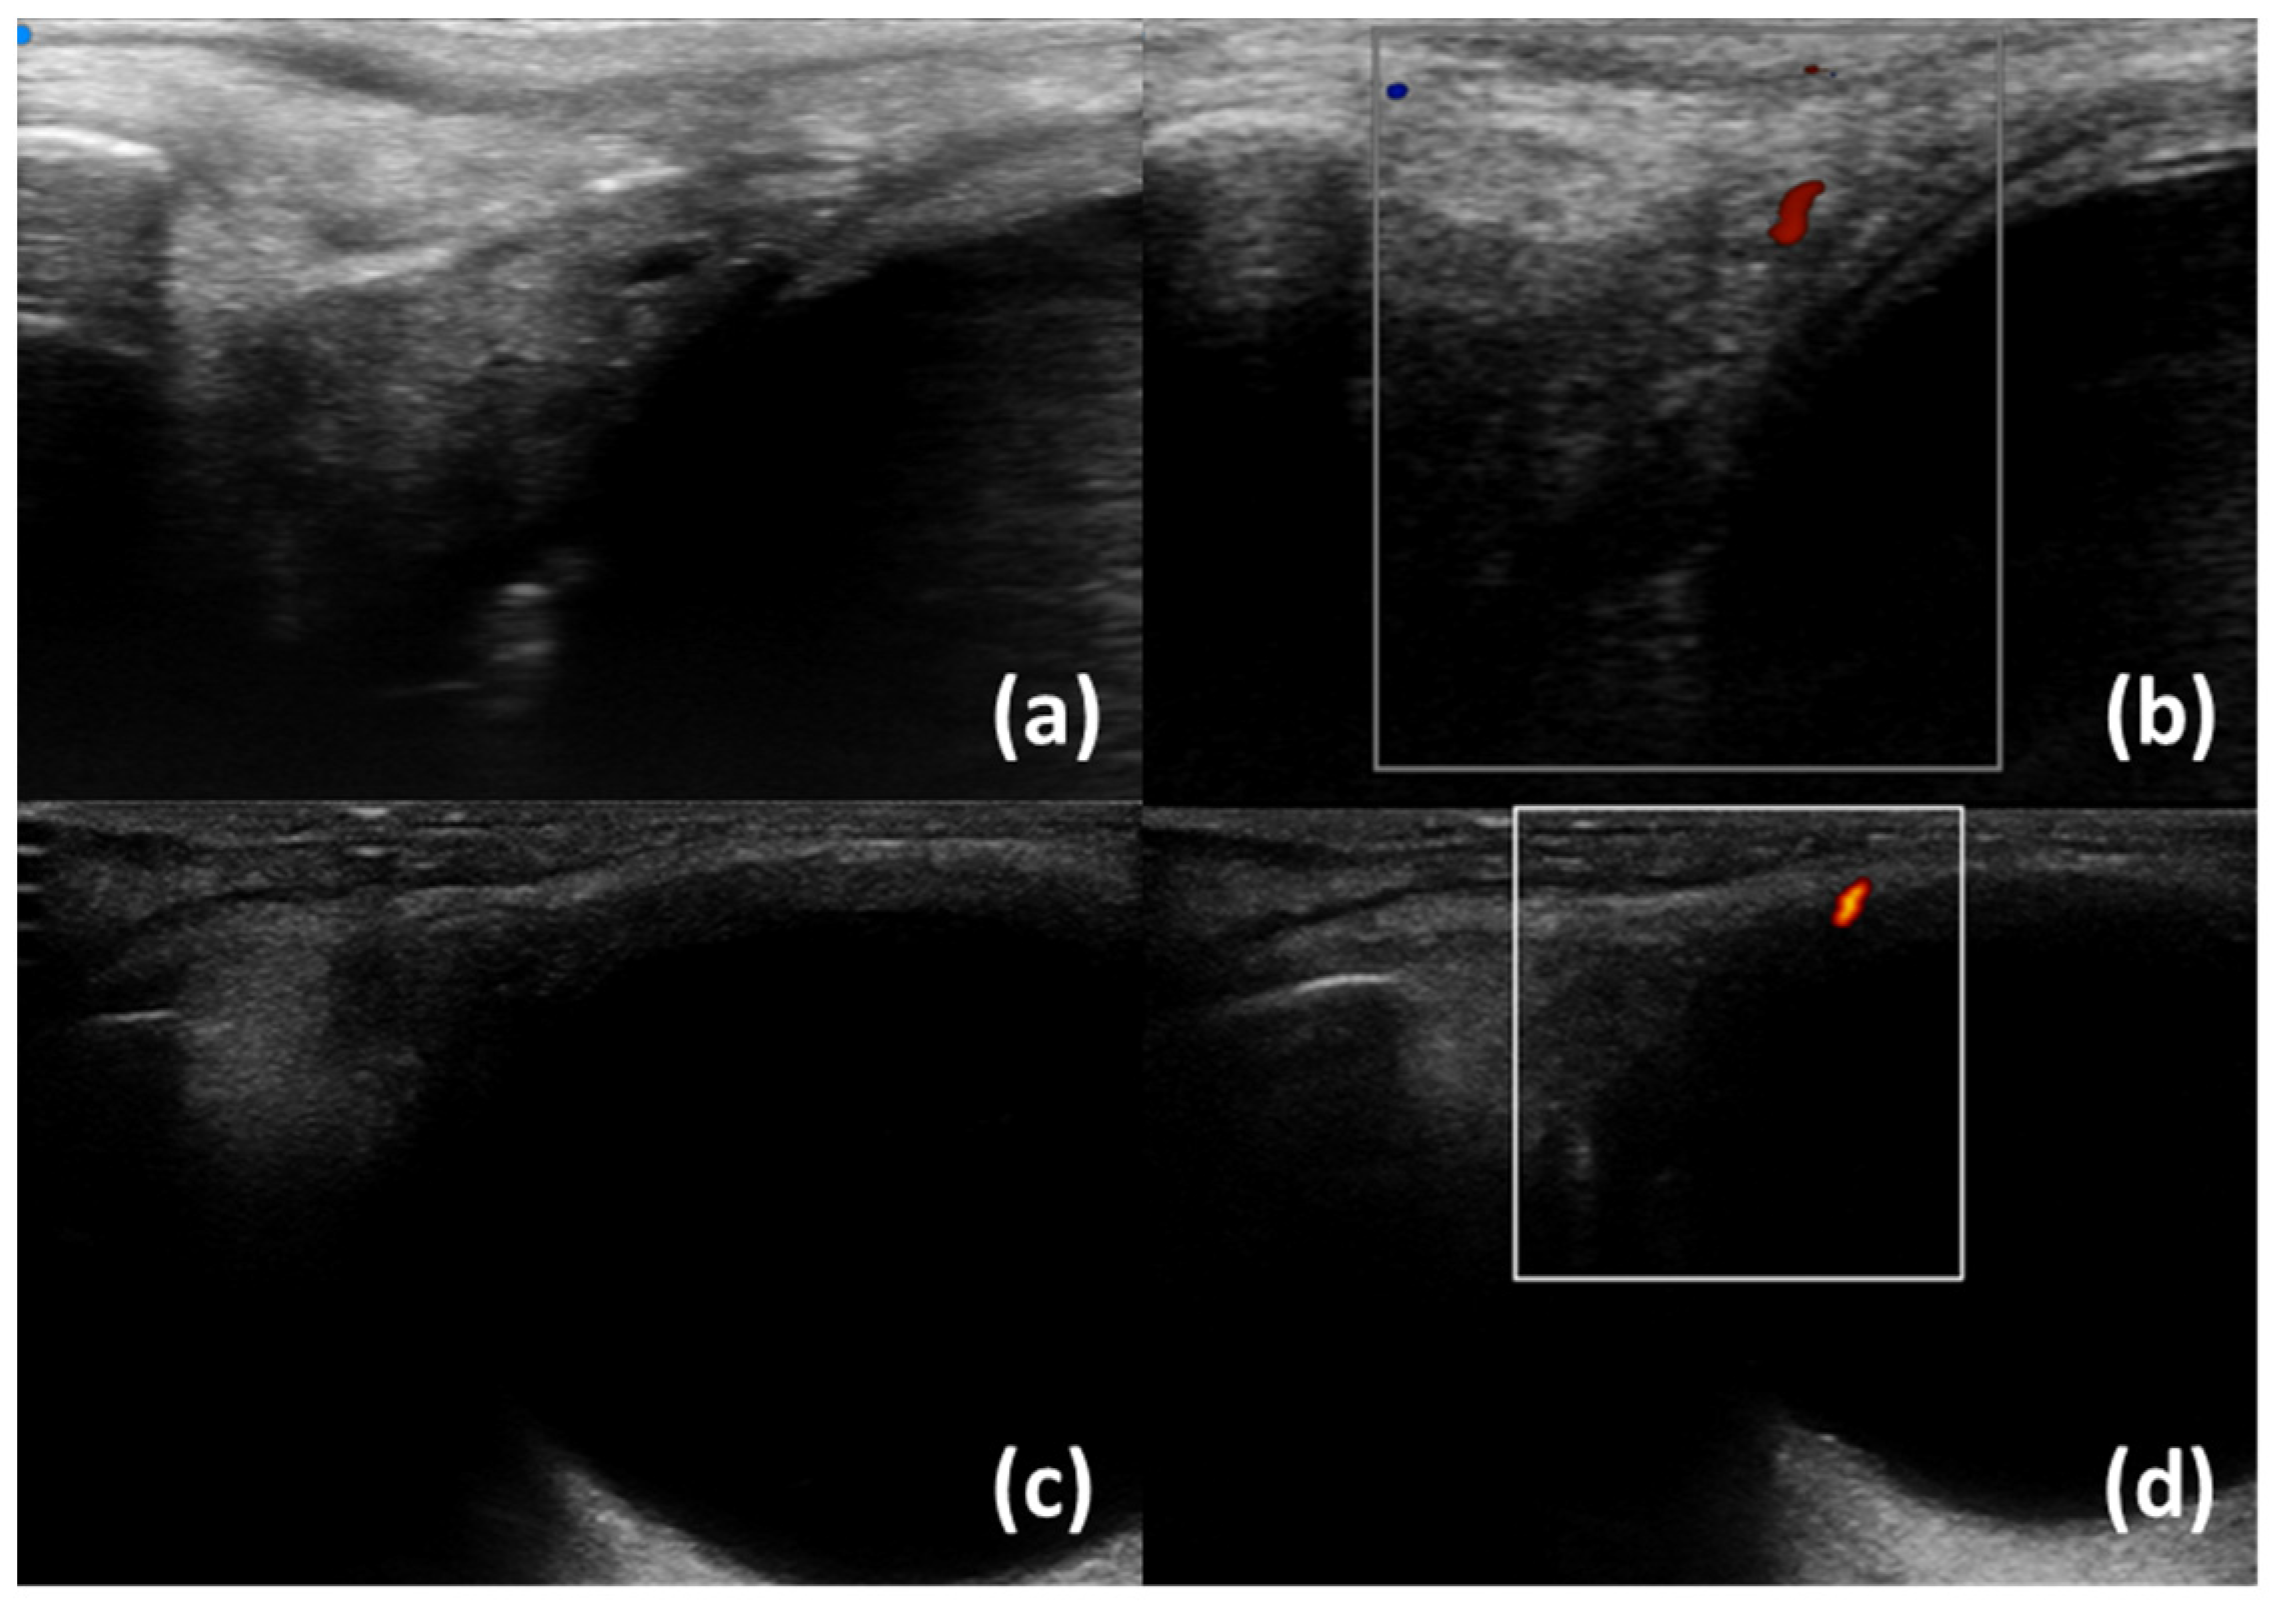

- Aringhieri, G.; Izzetti, R.; Vitali, S.; Ferro, F.; Gabriele, M.; Baldini, C.; Caramella, D. Ultra-high frequency ultrasound (UHFUS) applications in Sjogren syndrome: Narrative review and current concepts. Gland. Surg. 2020, 9, 2248–2259. [Google Scholar] [CrossRef] [PubMed]

- Fulvio, G.; Ferro, F.; Izzetti, R.; Governato, G.; Fonzetti, S.; La Rocca, G.; García, I.C.N.; Donati, V.; Mosca, M.; Baldini, C. POS1461 advantages of doppler in labial salivary gland ultra-high frequency ultrasound: Correlations with histological inflammation, pSS diagnosis, disease activity, and prognosis. Ann. Rheum. Dis. 2023, 82 (Suppl. S1), 1085. [Google Scholar] [CrossRef]